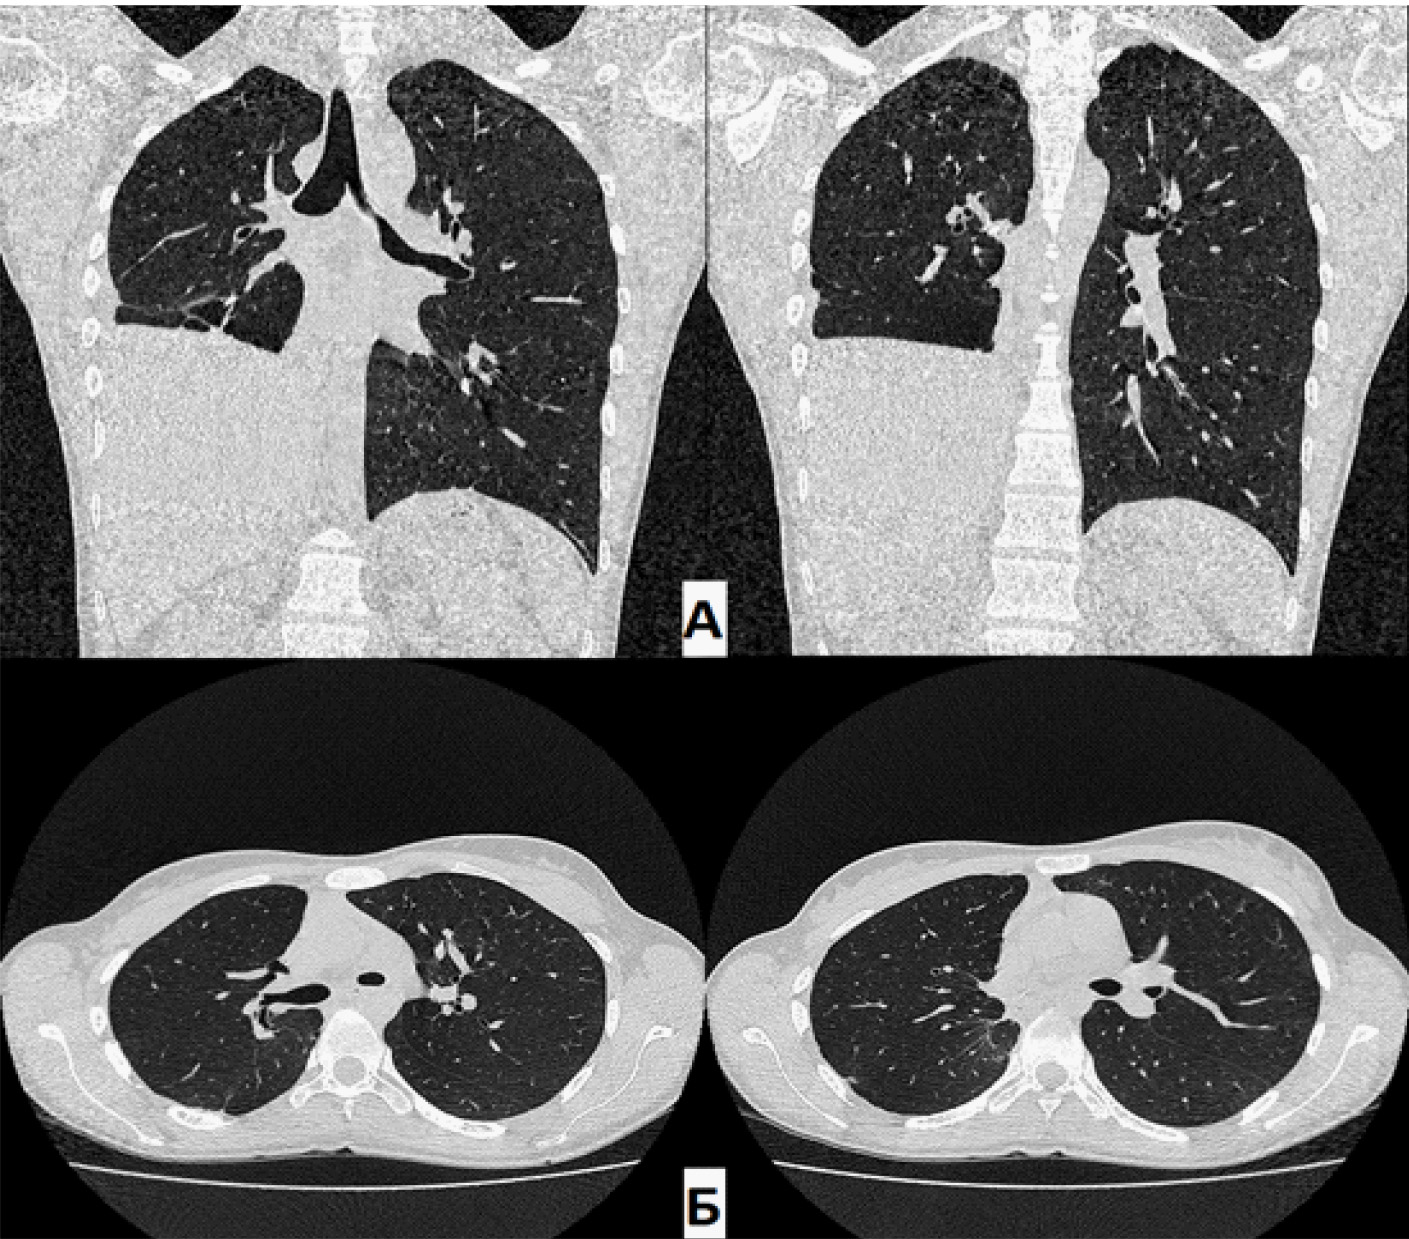

При контрольном КТ ОГК через 1,5 года: в динамике – полное отсутствие ОПП. Состояние после этапного хирургического лечения. В оставшихся отделах правого легкого без патологических изменений. Эмфизематозные изменения верхней доли правого легкого. Тень средостения располагается срединно, правый купол диафрагмы приподнят до уровня V межреберья.

Рис. 5. Компьютерная томография (А – фронтальная проекция; Б – аксиальная проекция) через 1,5 года. Отсутствие остаточной плевральной полости справа